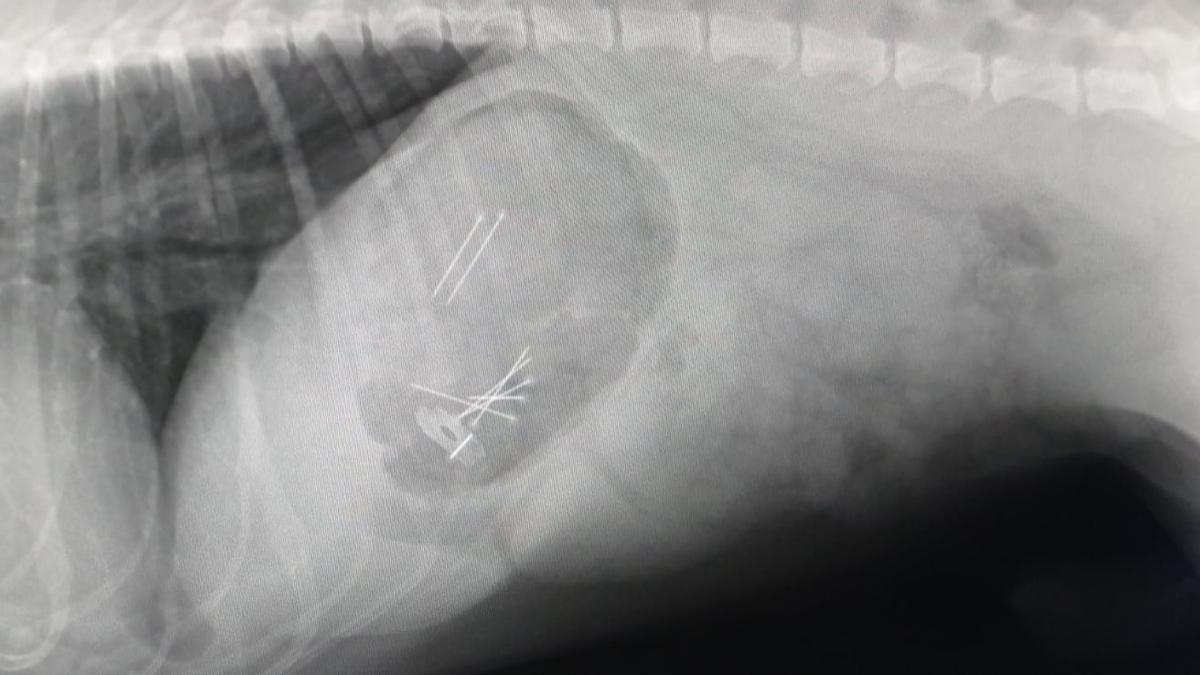

Una vecina de Vigo ha denunciado ante la unidad del Seprona de la Guardia Civil el envenenamiento de sus dos perros el pasado día 22. El matrimonio comprobó que una de sus mascotas presentaba la lengua negra y se encontraba sofocado, por lo que acudieron con él al veterinario. Ahí fue donde comprobaron que el animal había consumido múltiples pastillas de Paracetamol así como hasta ocho alfileres y una cuchilla de afeitar. El can tuvo que ser operado en una clínica de Padrón, donde pudieron salvarle la vida "de milagro", tal y como indica Marta, su propietaria.

El susto fue después cuando llegaron a casa y se encontraron a su otro animal con los mismos síntomas. En su caso, al tratarse de un perro de gran tamaño, la veterinaria de Vigo logró que pudiera devolver todo lo ingerido encontrándose más pastillas y otras siete agujas. Todo apunta que los animales ingirieron los alfileres mezclados con comida, por lo que la dueña de los animales ya presentó la correspondiente denuncia ante el Seprona para dar con los responsables del envenenamiento.